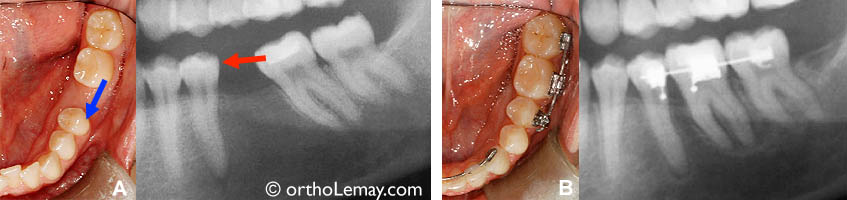

Espaces postérieurs

Molaire inférieure récemment extraite. Fermeture d’un espace d’extraction de 11 mm ce qui évite de faire remplacer cette molaire.